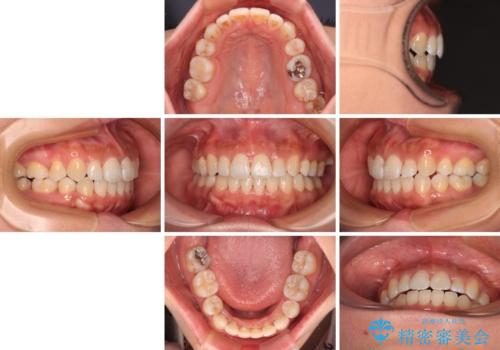

- 上下前歯のデコボコを気にして来院された患者様です。

右上と左下の小臼歯が1本ずつ欠損しており、奥歯の咬み合わせが乱れている状態でした。

バランスを取るために右下と左上の小臼歯を1本ずつ抜歯し、移動のための固定源としてアンカースクリューを利用してワイヤー装置による矯正治療を行うこととしました。

骨格的な左右差があり、上下正中をぴったり合わせることは難しく、奥歯の咬み合わせの調整にも時間がかかりましたが、きれいに整えることができました。